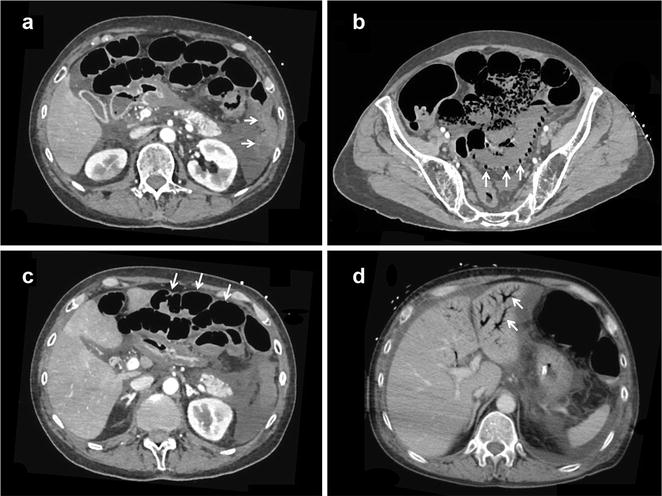

Two radiologists (AO and HG) blinded from the final diagnosis reviewed all abdominal CT-scans. Multidetector CT-scan were first carried out without contrast and secondarily contrast-enhanced with early (arterial time 30 s) and delayed (portal venous time 60–70 s) acquisitions following intravenous contrast medium infusion. The following radiological signs were systematically collected: pneumatosis intestinalis defined by the presence of gas inside the bowel’s walls, bowel dilatation, portal venous gas, aortic or mesenteric atherosclerosis, lack or heterogeneity of contrast-induced enhancement of bowel’s walls (Fig. 1). All eventual operative and endoscopic report forms were reviewed by investigators (GG and SL) blinded from the CT-scan findings. Regardless of CT-scan, only undisputed mesenteric ischemia diagnosed by surgical or endoscopic explorations were classified as definite NOMI. Extensive ischemia was defined as digestive ischemia involving more than one digestive segment. Conversely, NOMI was ruled out when neither surgical nor endoscopic explorations retrieved macroscopic evidence of digestive ischemia.

Fig. 1.

Representative CT-scan findings of non-occlusive mesenteric ischemia. a Absence of contrast-induced bowel wall enhancement (arrows). b Pneumatosis intestinalis and absence of contrast-induced bowel wall enhancement (arrows). c Bowel dilatation and absence of contrast-induced bowel wall enhancement (arrows). d Portal venous gas (arrows)